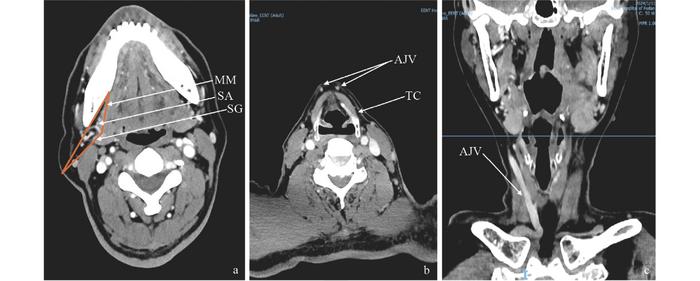

Vascular localization method in CT imaging

This research, published in ENT Discovery, introduces a systematic preoperative assessment protocol using computed tomography angiography (CTA). The study by Yangyang Ji and colleagues analyzed a large patient cohort to define and categorize the anatomical variations of the submental artery, particularly its origin from the facial artery. The developed standardized protocol enables precise visualization of the vascular course, caliber, and relationship to key anatomical landmarks. By identifying dominant patterns and potential anomalies, it allows surgeons to tailor their approach, minimize intraoperative surprises, and optimize flap design for individual patients.